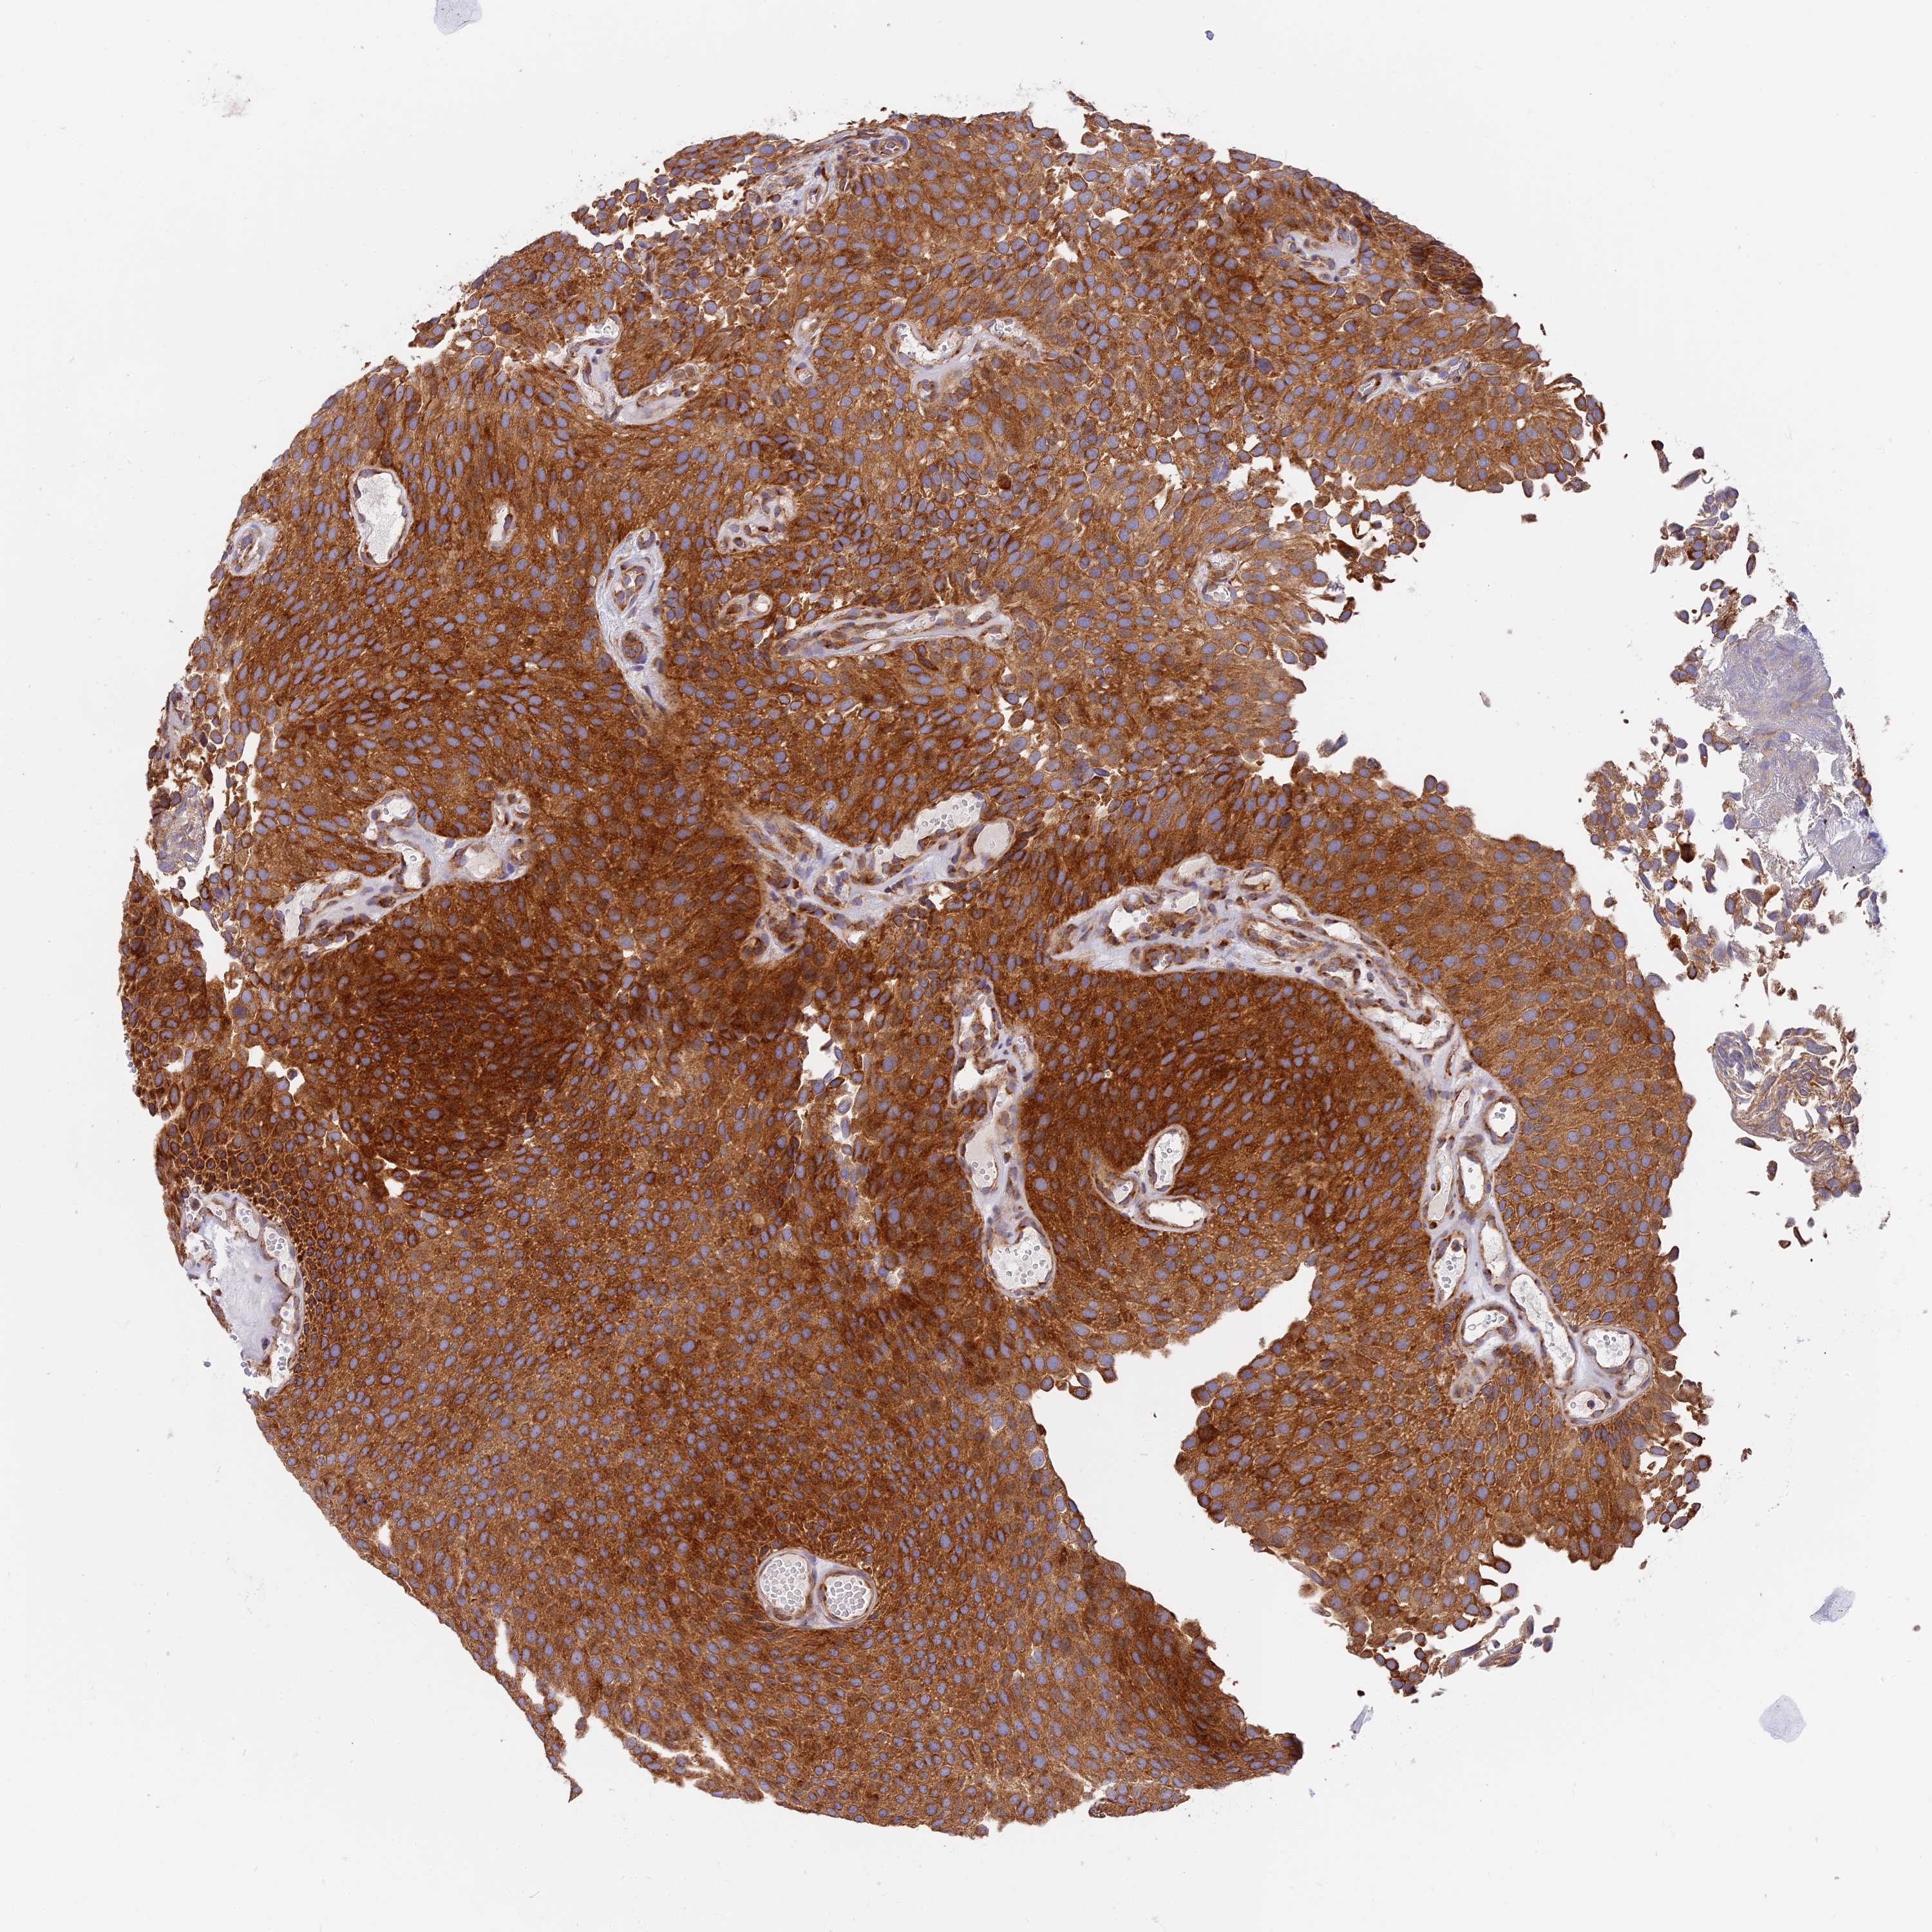

UROTHELIAL CANCER - Protein expressioni

A mouse-over function shows sample information and annotation data. Click on an image to view it in a full screen mode. Samples can be filtered based on level of antibody staining by selecting one or several of the following categories: high, medium, low and not detected. The assay and annotation is described here.

Antibody stainingi

Antibody staining in the annotated cell types in the current human tissue is reported as not detected, low, medium, or high, based on conventional immunohistochemistry profiling in selected tissues. This score is based on the combination of the staining intensity and fraction of stained cells.

Each image is clickable and will lead to virtual microscopy that enables deeper exploration of all samples and also displays staining intensity scores, fraction scores and subcellular localization as well as patient and tissue information for each sample.

Antibody HPA042728

Staining

High

Medium

Low

Not detected

Intensity

Strong

Moderate

Weak

Negative

Quantity

>75%

75%-25%

<25%

None

Location

Nuclear

Cytoplasmic/membranous

Cytoplasmic/membranous,nuclear

Urothelial carcinoma, High grade

Urothelial carcinoma, Low grade